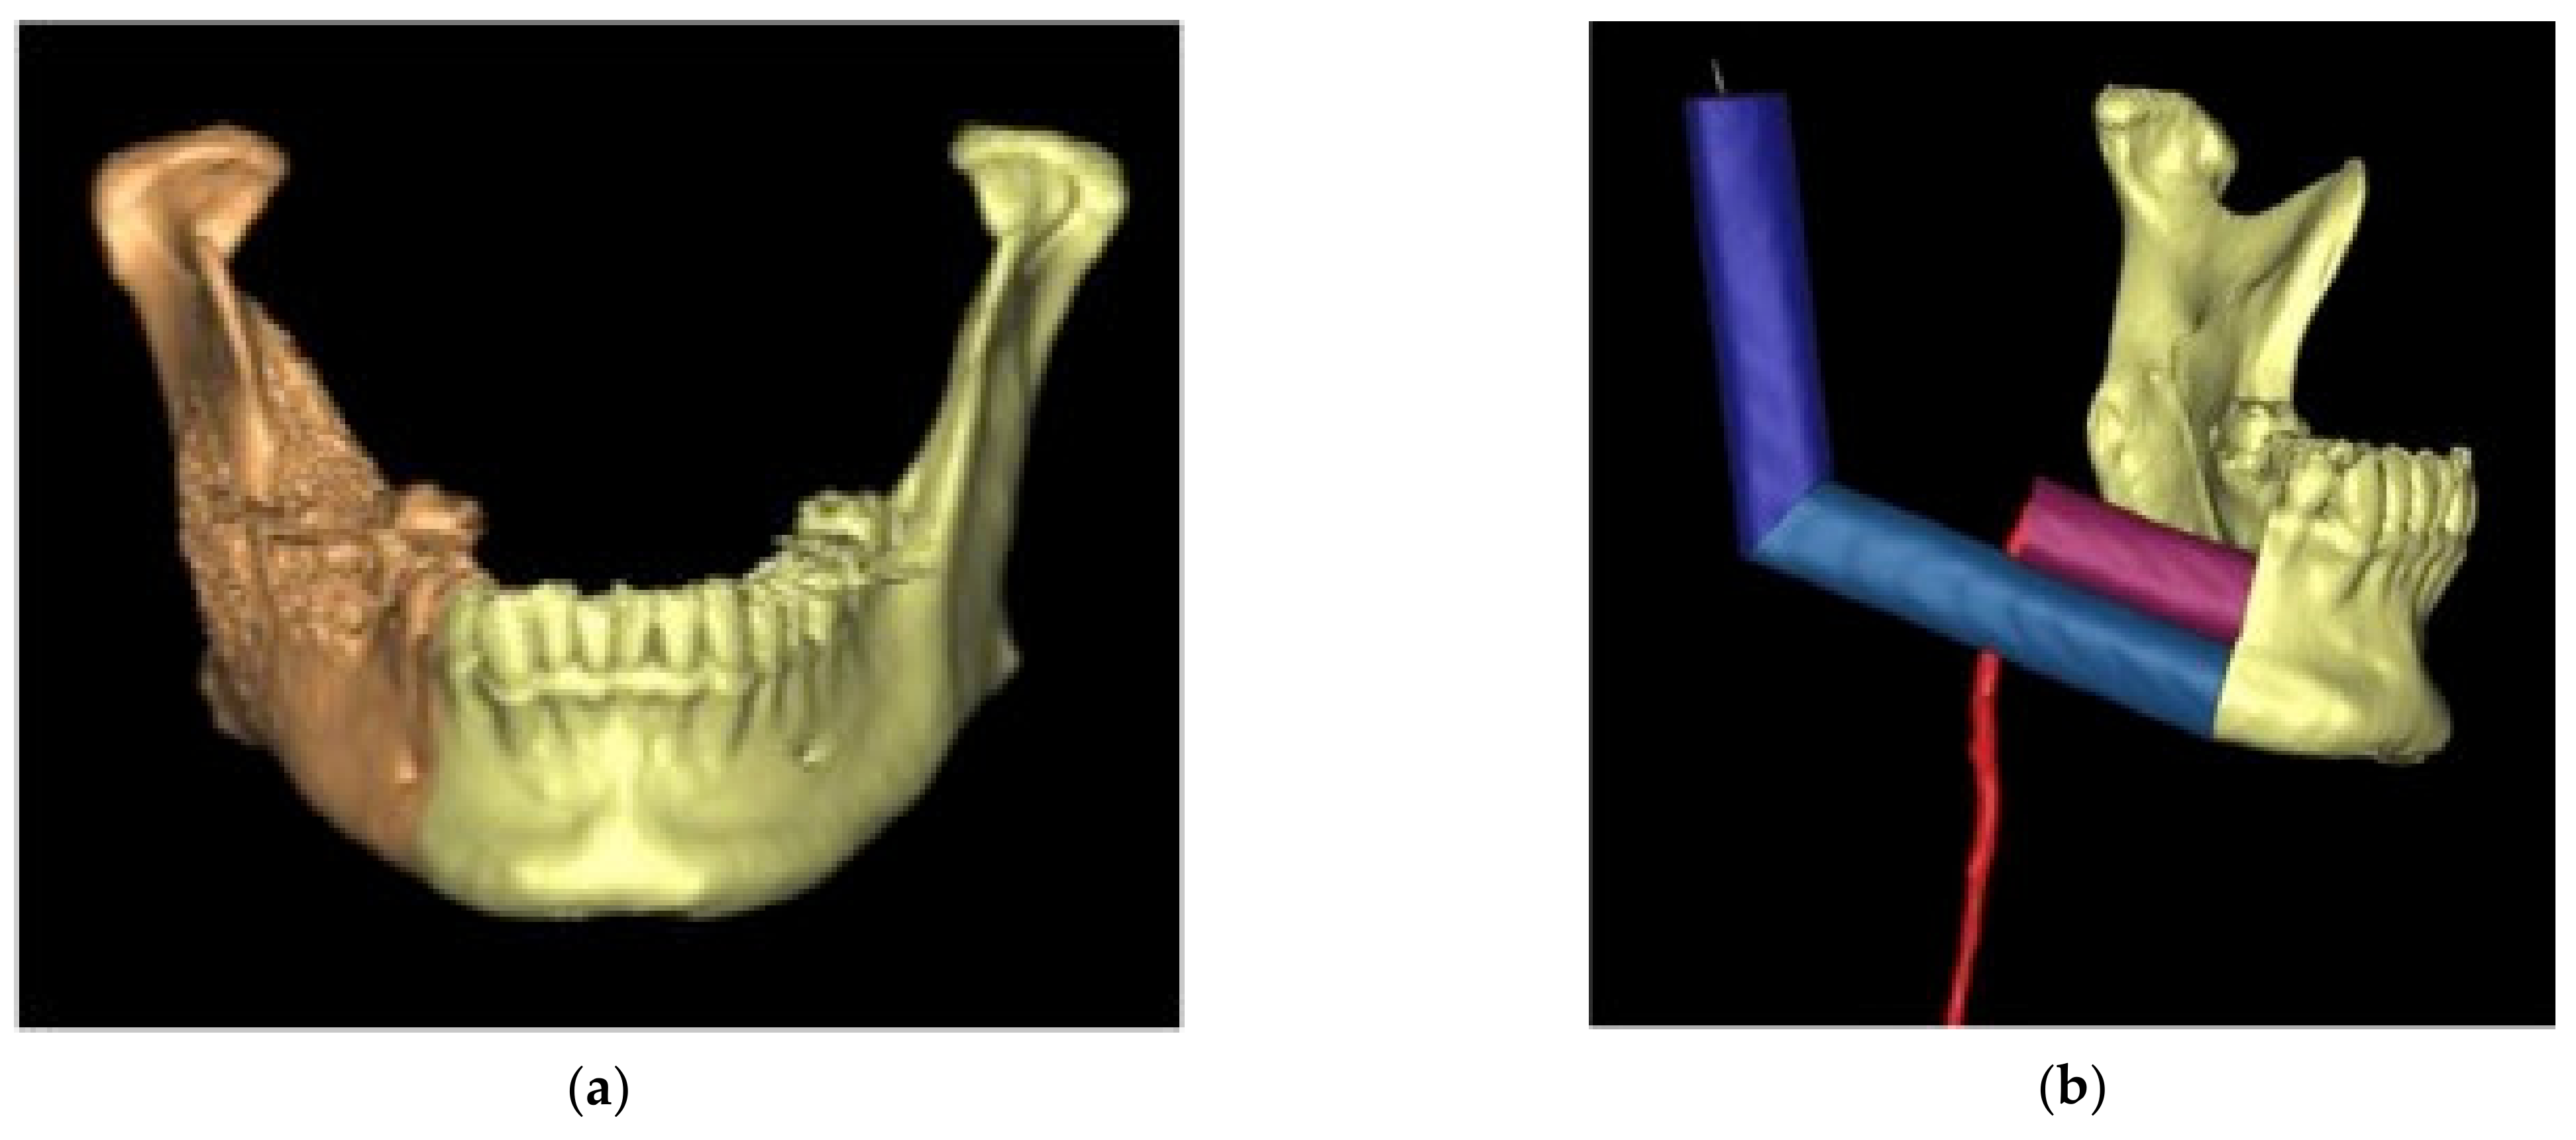

2.2. Virtual Planning

2.3. 3D Model Printing and Plate Shaping

2.4. Pre-Surgical Navigation: 3D Model Registration

2.5. Intra-Operative Surgical Navigation